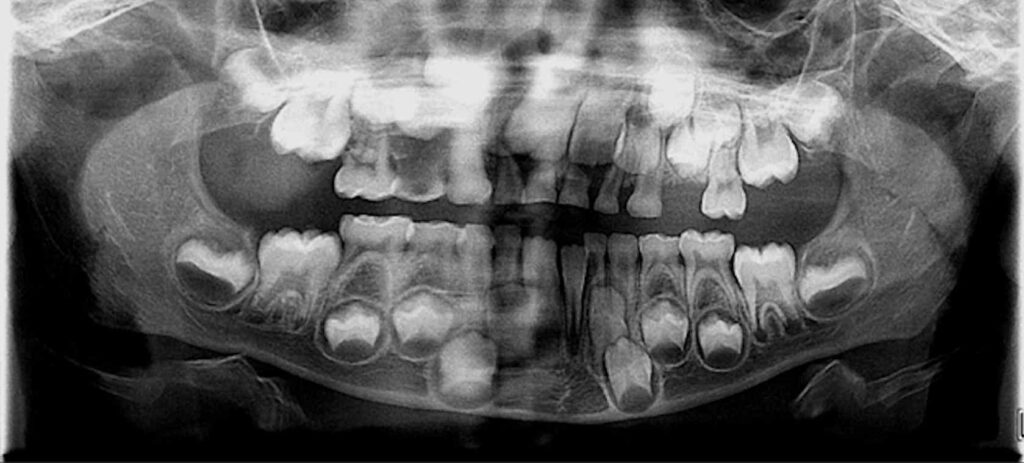

7-year-old boy with multiple oral lesions

A 7-year-old boy presented to the family dentist with multiple lesions in his mouth.